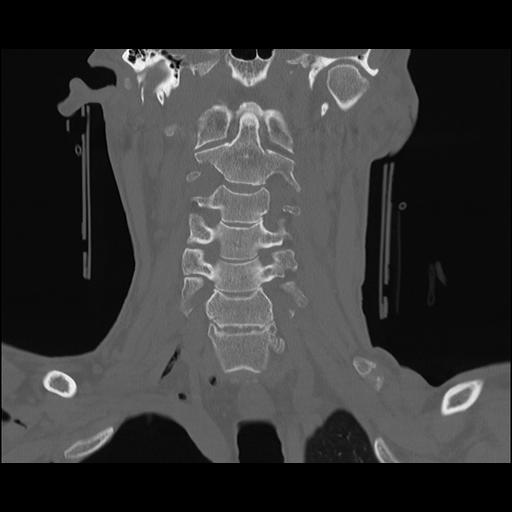

16 HUESO,,Coronal,2.000,HUESO,Coronal,